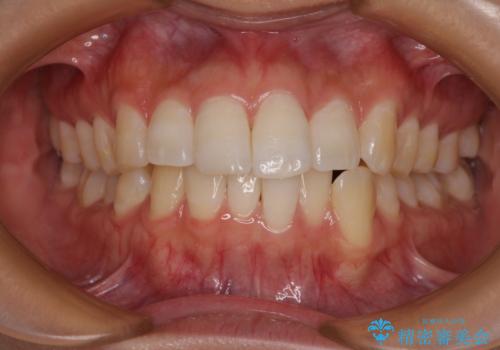

インビザライン・モデレートを用いて気になる後戻りを矯正治療

担当医 藤巻太一朗

前歯のガタつきを改善 抜歯矯正後の後戻り

担当医 草深敏毅